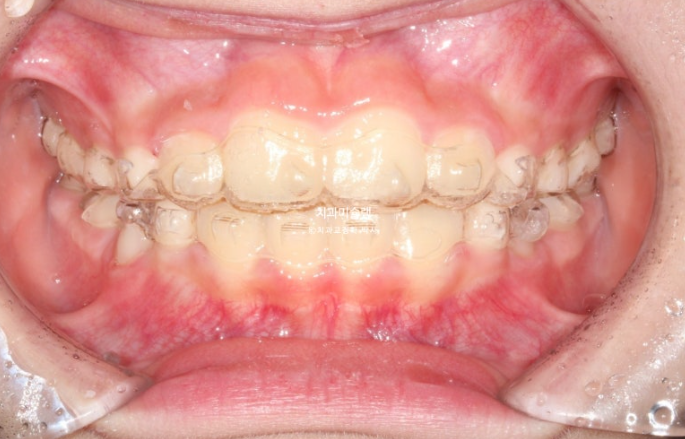

인비절라인 퍼스트 치료에 들어갔습니다.

첫세트 장치는 23개 입니다.

5개월간 23개 장치를 모두 낀 후 모습입니다.

24.05

과개교합은 개선되었고 측절치 나올 공간을 악궁확장으로 미리 벌려줬기 때문에 측절치는 잘 내려왔습니다.